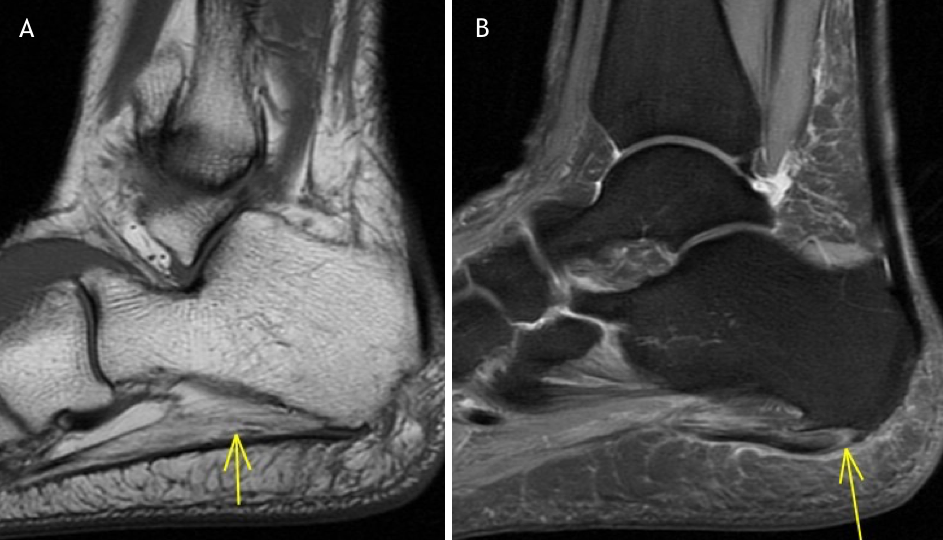

From radiopaedia.org

Baxter neuropathy Image Baxter's Nerve Neuropathy Also known as calcaneal nerve entrapment, baxter’s neuritis occurs when a branch of the tarsal tunnel nerves becomes trapped or scarred. Baxter’s nerve entrapment or baxter’s neuropathy, often overshadowed by the more commonly discussed plantar fasciitis, emerges as a pivotal culprit behind chronic. Find out how to identify baxter's neuropathy. Plantar fasciitis or heel spurs are the most common cause. Baxter's Nerve Neuropathy.

Baxter neuropathy Image Baxter's Nerve Neuropathy Baxter’s nerve is a mixed. Baxter’s nerve entrapment or baxter’s neuropathy, often overshadowed by the more commonly discussed plantar fasciitis, emerges as a pivotal culprit behind chronic. Find out how to identify baxter's neuropathy. Also known as calcaneal nerve entrapment, baxter’s neuritis occurs when a branch of the tarsal tunnel nerves becomes trapped or scarred. Baxter’s neuropathy is a condition. Baxter's Nerve Neuropathy.